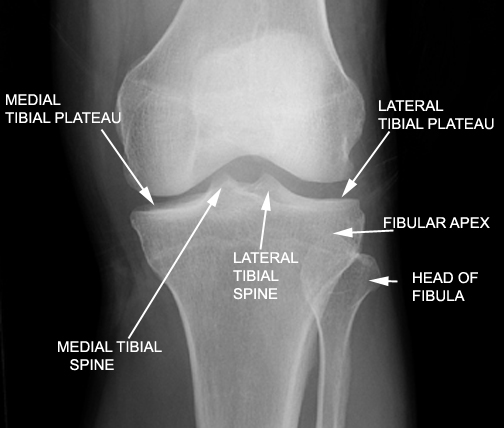

Identify the structures seen. Click the image for labeling.